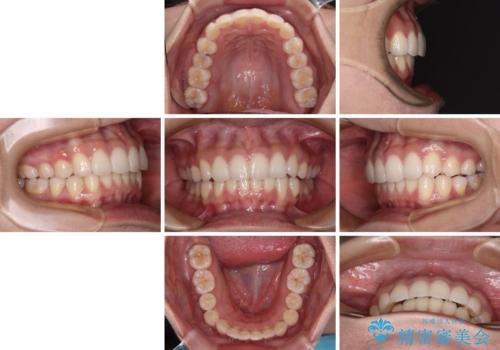

- 前歯のデコボコを治したいとのことで来院された患者様です。

上下顎ともに歯列全体の後方移動とIPR(歯と歯の間を削る)によってデコボコが解消するように設計し、インビザラインにより治療を行うこととしました。

上下ともにIPRを積極的に行っているため、舌の突出癖をしっかりと改善できないと、後戻りにより隙間やデコボコが早い段階で発現することになるため、舌のトレーニングが非常に大切になります。